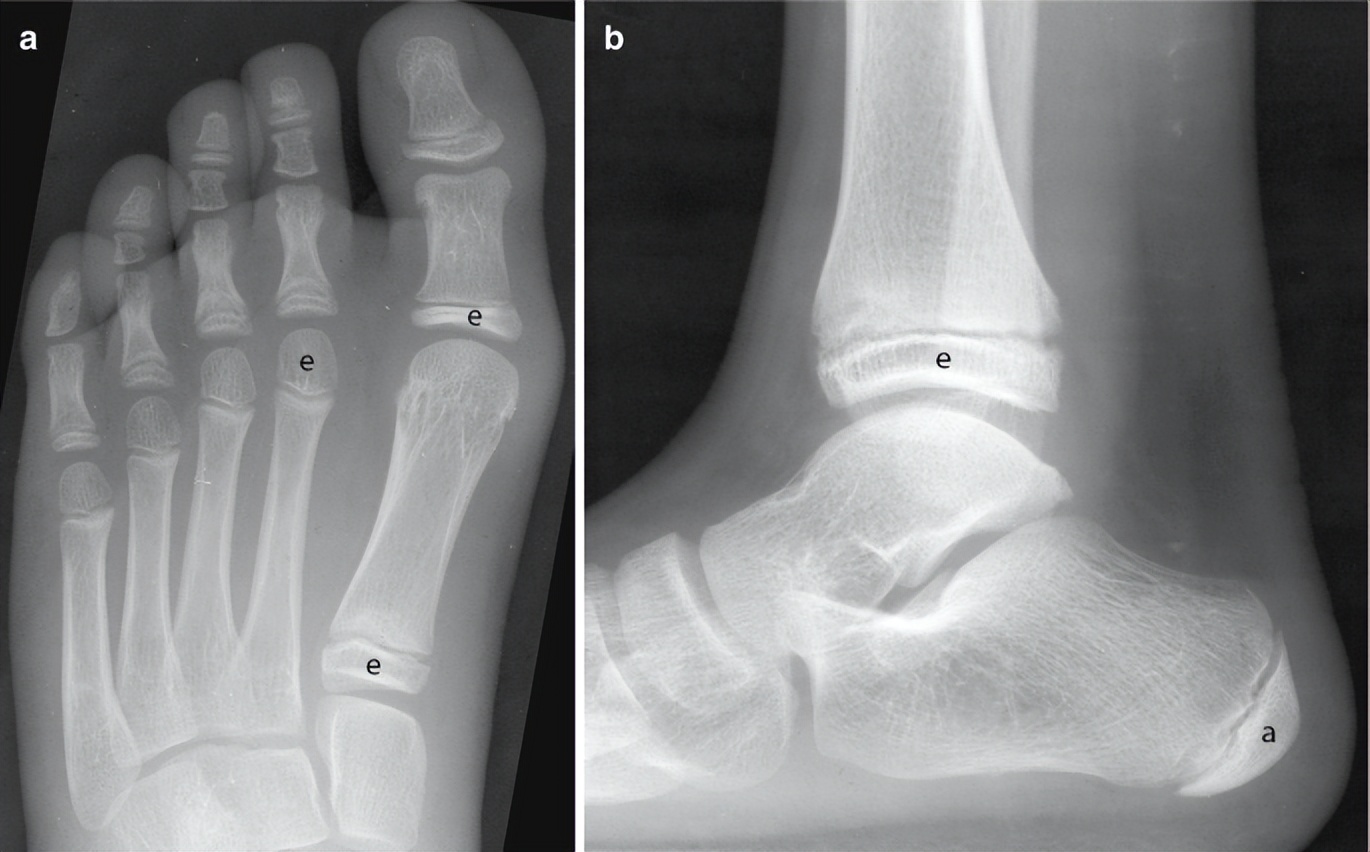

这是一个拇外翻家长给我发过来孩子脚的情况,他们家孩子12岁,非常典型的拇外翻,她就问我孩子现在12岁,这种情况可不可以做拇外翻手术。如果说你的孩子也有踇外翻,现在该做哪些事情我们权且不讲,有这么严重的,十一二岁有这么严重的还是非常少见。我在临床十多年,见到孩子,十一二岁孩子如此严重的不太多,这是个例。